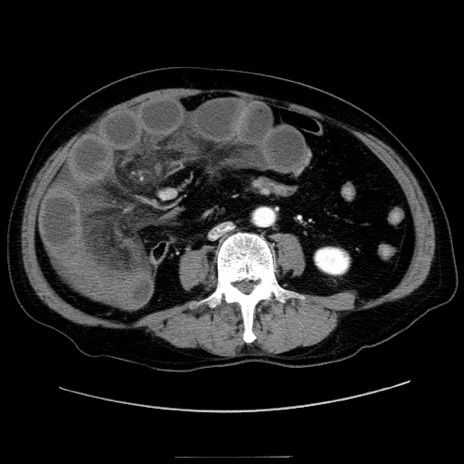

症例30(横断像)

冠状断像

【症例】80歳代男性

【現病歴】約6時間前から臍下部痛が出現。次第に腹部膨隆・背部痛も生じてきたため来院。背部痛の場所は変化しない。

【身体所見】意識清明、BT 36.3℃、BP  131/87mmHg、P 87bpm、SpO2 100%(RA)、臍周囲自発痛・圧痛あり、反跳痛なし、自発痛部位に一致して板状硬あり、腹部膨隆、腸雑音減弱、CVA tenderness両側陰性。